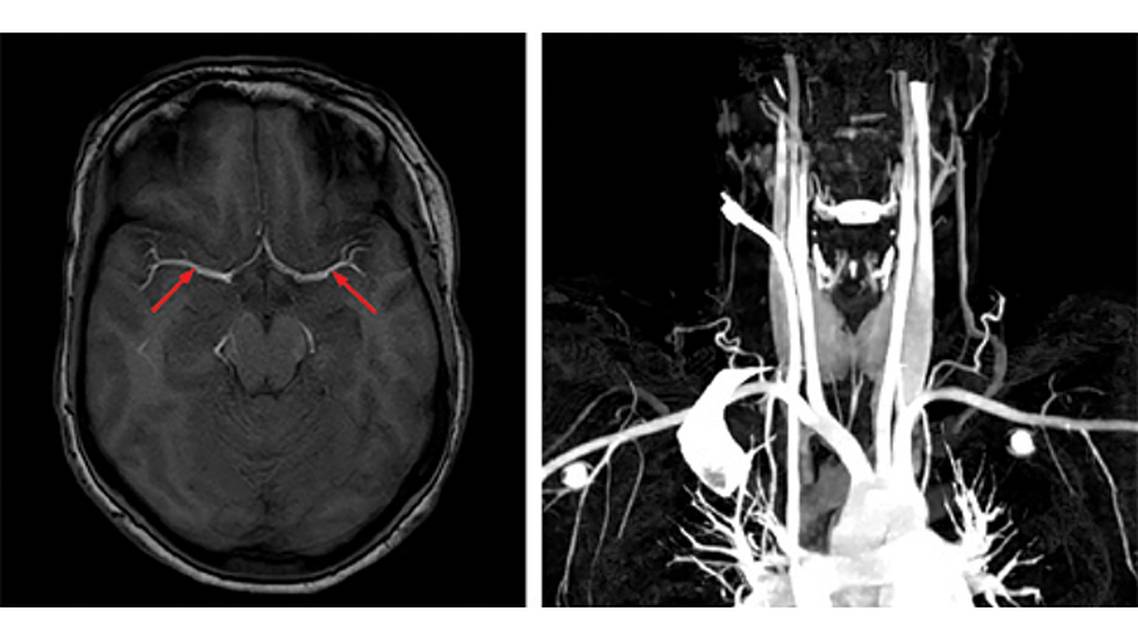

FG’s routine blood tests returned normal results, and electrocardiogram and transthoracic echocardiogram tests showed no abnormalities. Brain CT scan showed no pathologic findings. But the following brain MRI revealed ischemic infarction in the right frontal lobe, predominantly affecting the territory of the right anterior cerebral artery (ACA), the head of the caudate nucleus, and the corpus callosum (Figure 1). Additional imaging, including brain and neck CT angiography (Figure 2), revealed no large vessel occlusions (including in the internal carotid artery [ICA] and middle cerebral artery [MCA]). Therefore, no further interventions were deemed necessary. Medical treatment with anticoagulant was initiated despite a lack of approved indications with this type of presentation.